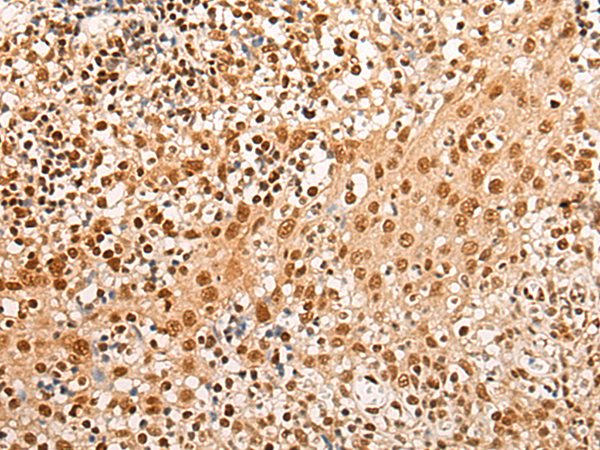

分类: 科研抗体货号: P13219别名: CDP; CUX; p75; CASP; CDP1; COY1; Clox; p100; p110; p200; CUTL1; GOLIM6; CDP/Cut; Cux/CDP; Nbla10317应用: IHC反应种属: Human, Mouse, Rat